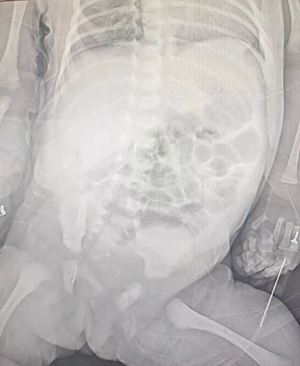

△腹部影像提示隱蔽性腹部出血

接診后,醫(yī)院立即啟動多學(xué)科協(xié)作機(jī)制,新生兒外科主任宋華團(tuán)隊(duì)第一時間前往會診。結(jié)合患兒胎兒期產(chǎn)檢就發(fā)現(xiàn)右下腹 3 厘米大小囊性回聲的病史,查體時面色及軀干部皮膚蒼黃的表現(xiàn),以及超聲、影像等提示的各項(xiàng)異常,團(tuán)隊(duì)初步診斷為腹腔隱匿出血、腸扭轉(zhuǎn)、黃疸、貧血,建議盡快手術(shù)干預(yù)。